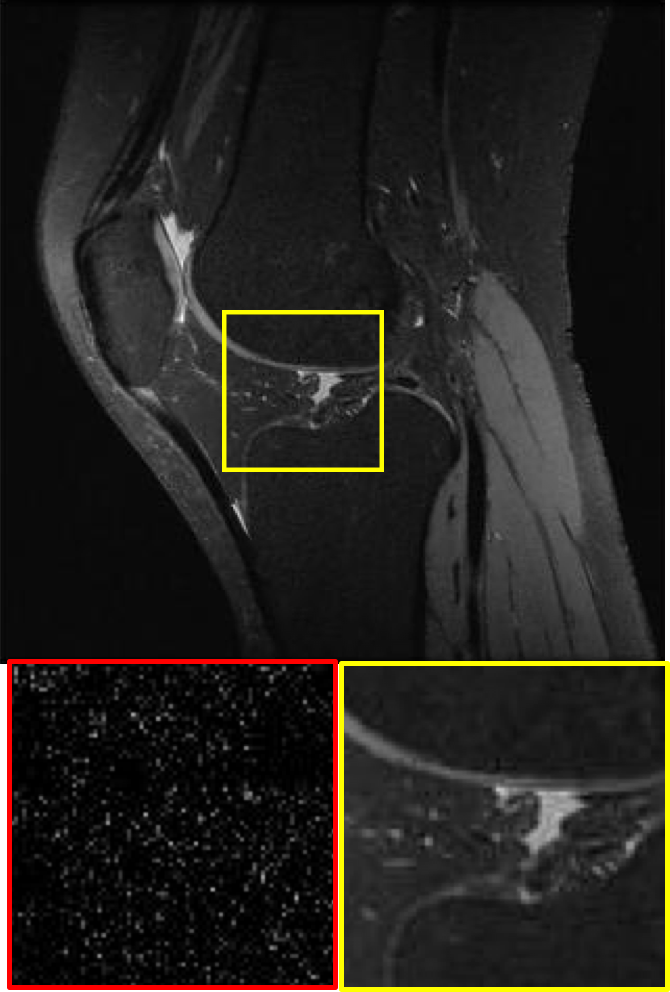

CS MR measurement matrix

LDAMP SURE was applied to CS-MRI reconstruction problem to demonstrate its generality and to show its performance on images that contain structures different from natural image dataset. We compared LDAMP SURE with state-of-the-art BM3D-AMP-MRI algorithm [16] for CS-MR image reconstruction along with TVAL3, BM3D-AMP, and dictionary learning method or DL-MRI [34]. Average image recovery PSNRs and run times are tabulated in Table 3. Figure 5 shows that our proposed method yielded state-of-the-art performance, close to the ground truth. The results reveal that proposed LDAMP SURE-T outperforms existing algorithms in all sampling ratios.

Ground truth

TVAL3

BM3D-AMP

DL-MRI

BM3D-AMP-MRI

LDAMP SURE-T